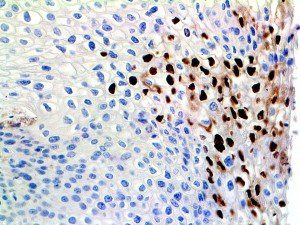

The first cytokines released are interleukin 1β (IL-1β) and tumor necrosis factor-α (TNF-α), which attract a variety of circulating white blood cells (WBCs) to the infection site, including neutrophils, monocytes, macrophages, and natural killer (NK) cells. This response, along with the antipathogenic chemicals released by these cells (i.e., complement), comprise the innate immune response. These cells directly attack the invading pathogen and also release additional cytokines, chief among them interleukin-1 and 6 (IL-6). IL-6 is essential for invoking the adaptive immune response, which calls T-cells, B-cells, and T helper (Th) cells to the infection site. IL-6 also stimulates further recruitment, proliferation and activation of macrophages.

It is the ICU physician who is most likely to witness one of the deadliest manifestations of the abnormal immunological response, the cytokine storm syndrome (CSS). This response is also referred to by some as the cytokine release syndrome (CRS). CSS is characterized by continuous activation and expansion of macrophage and lymphocyte populations, which secrete large amounts of cytokines, causing the cytokine storm. This massive cytokine release is akin to hemophagocytic lymphohistiocytosis (HLH) disease, a syndrome characterized by initial unchecked and persistent activation of cytotoxic T lymphocytes and NK cells.

Clinical and laboratory manifestations of HLH include fever, enlarged liver and/or spleen, neurologic dysfunction, coagulopathy, liver dysfunction, cytopenias (i.e., low levels of erythrocytes, leukocytes, and/or platelets), hypertriglyceridemia, hyperferritinemia, hemophagocytosis, and eventually diminished NK cell activity as the immune system becomes progressively paralyzed. HLH can be familial (primary HLH) or secondary to another disease process (sHLH), such as rheumatic disease, in which it is referred to as macrophage activation syndrome (MAS, characterized by elevated ferritin).